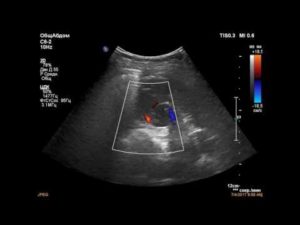

- УЗИ обеих почек – позволяет оценить размеры, структуру, однородность тканей органа, а также выявить имеющиеся уплотнения и определить их размер.

Основу диагностики опухоли почки составляют инструментальные методы обследования. Самым простым и доступным является УЗ-сканирование забрюшинного пространства. Во время УЗИ можно выявить объемное образование почек, оценить такие параметры, как:

- размер и структуру опухоли,

- деформацию контура почечной капсулы,

- наличие очагов кровооизлияния и некроза,

- состояние кровотока в образовании и самом органе,

- сопутствующие изменения со стороны мочевыводящих путей.

Ангиомиолипома может быть диагностирована случайно при прохождении УЗИ. На экране на фоне нормальной паренхимы четко просматривается уплотнение.

Данная методика позволяет оценить диаметр, эхогенность и структуру нароста.

- УЗИ. Помогает выявить уплотнение, оценить его диаметр и структуру;

- ангиография ультразвуковая. Необходима для определения сосудистых патологий, среди которых может быть аневризма и деформация;

- Исследование почек ультразвуком и допплерография. Ультразвук исследует место очага, его параметры, строение, с помощью УЗДГ определяют травмирование сосудов.